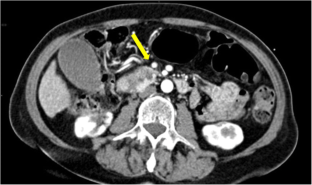

Fig. 1

Fig. 2

Fig. 3

Fig. 4